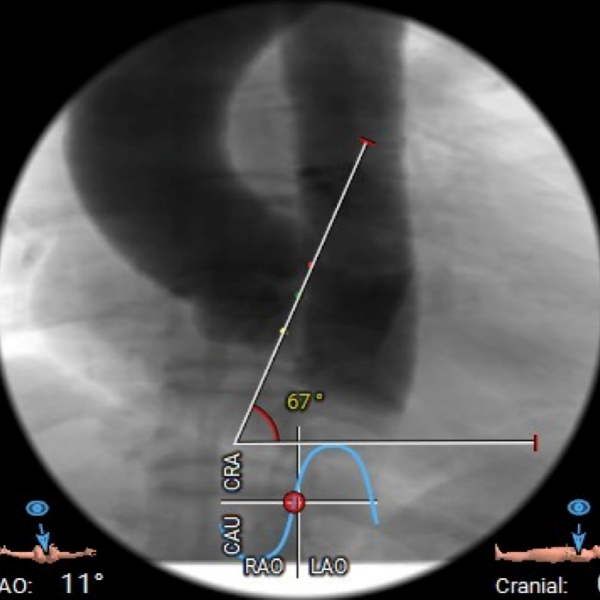

该患者为一例重度AS患者,双侧股动脉见环形钙化,外周入路挑战较大,手术风险高。主动脉瓣环水平夹角67度,横位心,假体瓣膜释放后有位移可能。

瓣环水平夹角

主动脉瓣瓣环周长66.2,平均周长径 21.1mm,SOV:32.2mm*36.4mm*34.1mm,瓣叶增厚,瓣上钙化分布不均,主动脉瓣环水平夹角67度,横位心。